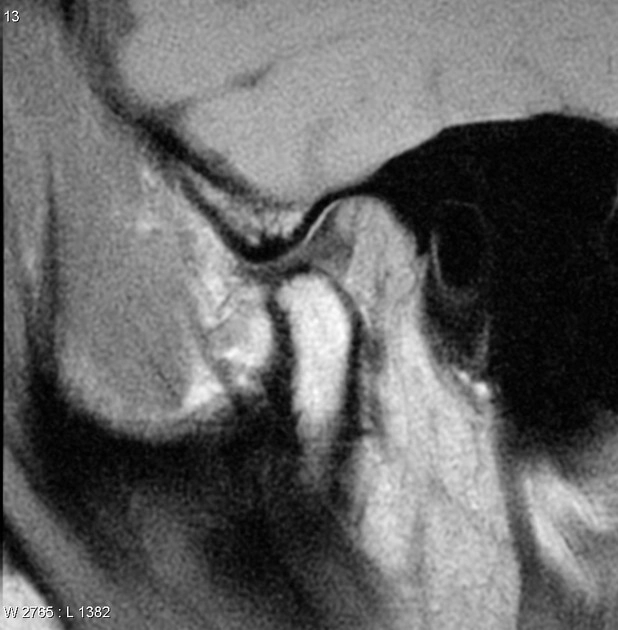

Thoái hóa khớp thái dương hàm (Osteoarthritis of the temporomandibular joint - TMJ OA)